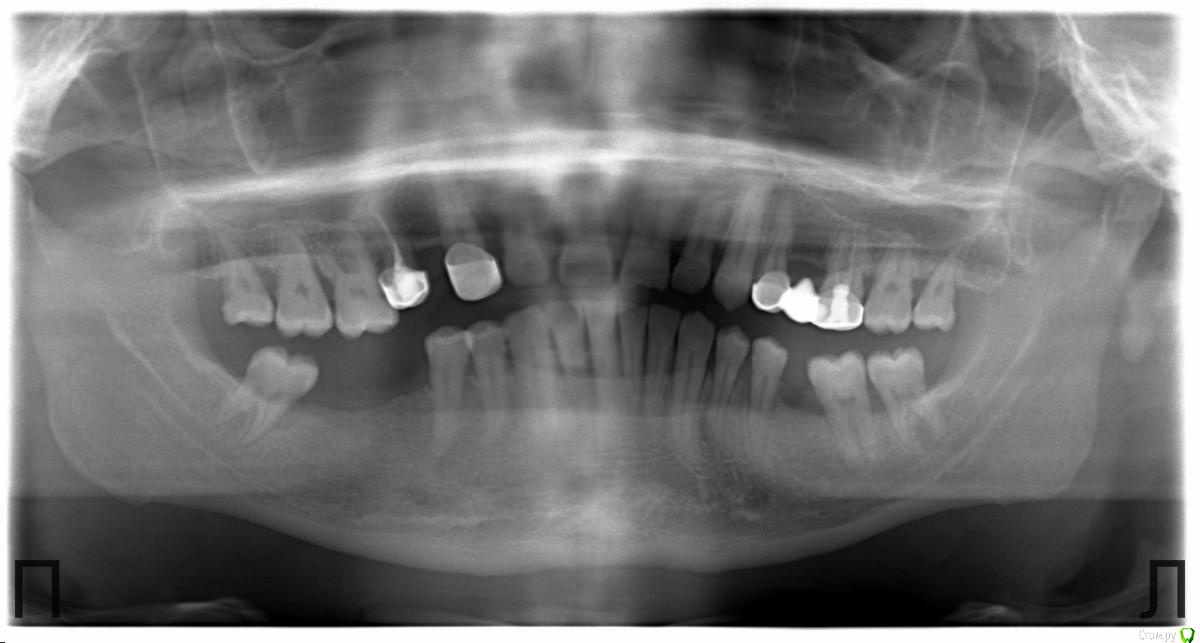

Corsag21 Опубликовано 5 июля, 2018 Поделиться Опубликовано 5 июля, 2018 (изменено) Штампанину на мороз бы выгнал для начала.Определил состояние пародонта: глубина карманов, зубодесневое прикрепление, etc...Ну и оттуда работать Что делать когда мы узнаем глубину карманов, зубодесневого прикрепления? По снимку ОПТГ видно что примерно 50% костной ткани есть и во рту нет оголения корней. Если зубы устойчивы, то можно несъемные делать. Хуже когда все зубы подвижны 1 степени и соматическое заболевание, я не знаю оптимального способа протезирования на эти случаи. Что-то мне кажется что у пациента сахарный диабет. Почему удаляете 1.6 - он неустойчив или периапикальная патология? Изменено 5 июля, 2018 пользователем Corsag21 Ссылка на комментарий

Витторио Орлионе Опубликовано 5 июля, 2018 Автор Поделиться Опубликовано 5 июля, 2018 Что делать когда мы узнаем глубину карманов, зубодесневого прикрепления? По снимку ОПТГ видно что примерно 50% костной ткани есть и во рту нет оголения корней. Если зубы устойчивы, то можно несъемные делать. Хуже когда все зубы подвижны 1 степени и соматическое заболевание, я не знаю оптимального способа протезирования на эти случаи. Что-то мне кажется что у пациента сахарный диабет. Почему удаляете 1.6 - он неустойчив или периапикальная патология?в четвёртом сегменте планируется мостовидный протез стало быть надо 1.6 брать под коронку, а бифуркация оголена и потому зуб всё таки пойдёт под удаление, к тому моменту уже будет стоять мостовидный протез 1.5-1.3 и единственный вариант это ставить имплант, нужен будет синуслифтинг, аааа удаление и удлинение мостовидного протеза до 1.7-1.5-1.3 будет более долгосрочной и логичной конструкции по мне, могу и ошибаться... Ссылка на комментарий

krokomot Опубликовано 5 июля, 2018 Поделиться Опубликовано 5 июля, 2018 если на зубе нет налета, отложений зубных и прочей бяки, стоит ли тогда лезть туда? А что делать если все зубы подвижны 1 степени и резорбция костной ткани почти 1\2 на всех зубах? Помогите с тактикой.Не бывает огня без дыма, если из кармана течет, значит там кто-то живёт, и запомните карманы без налета и флоры не образуются, есть карман,- есть проблемма. Тактика зависит от желания и возможностей пациента, при атрофии 1\2 вы не получите идеальную бело-розувую эстетику, в любом случае в чем то будет компромис, на начальном этапе всегда веду таких пациентов поэтапно, снала стабилизируем процесс, потом смотрим что на выходе отсюда и дальнейшая тактика с протезированием, но если пациента не вывести из margin periodontitis? то о каком протезировании может идти речь? и темболее никаких мостов уже не может быть, одиночки плюс съемник или же одиночки плюс имплантаты, ну и на крайняк всё в топку и олл ин фо)) 1 Ссылка на комментарий